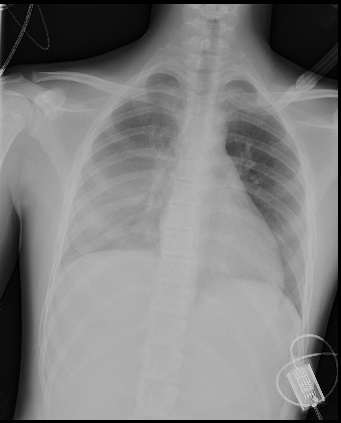

• Radiografía de tórax.